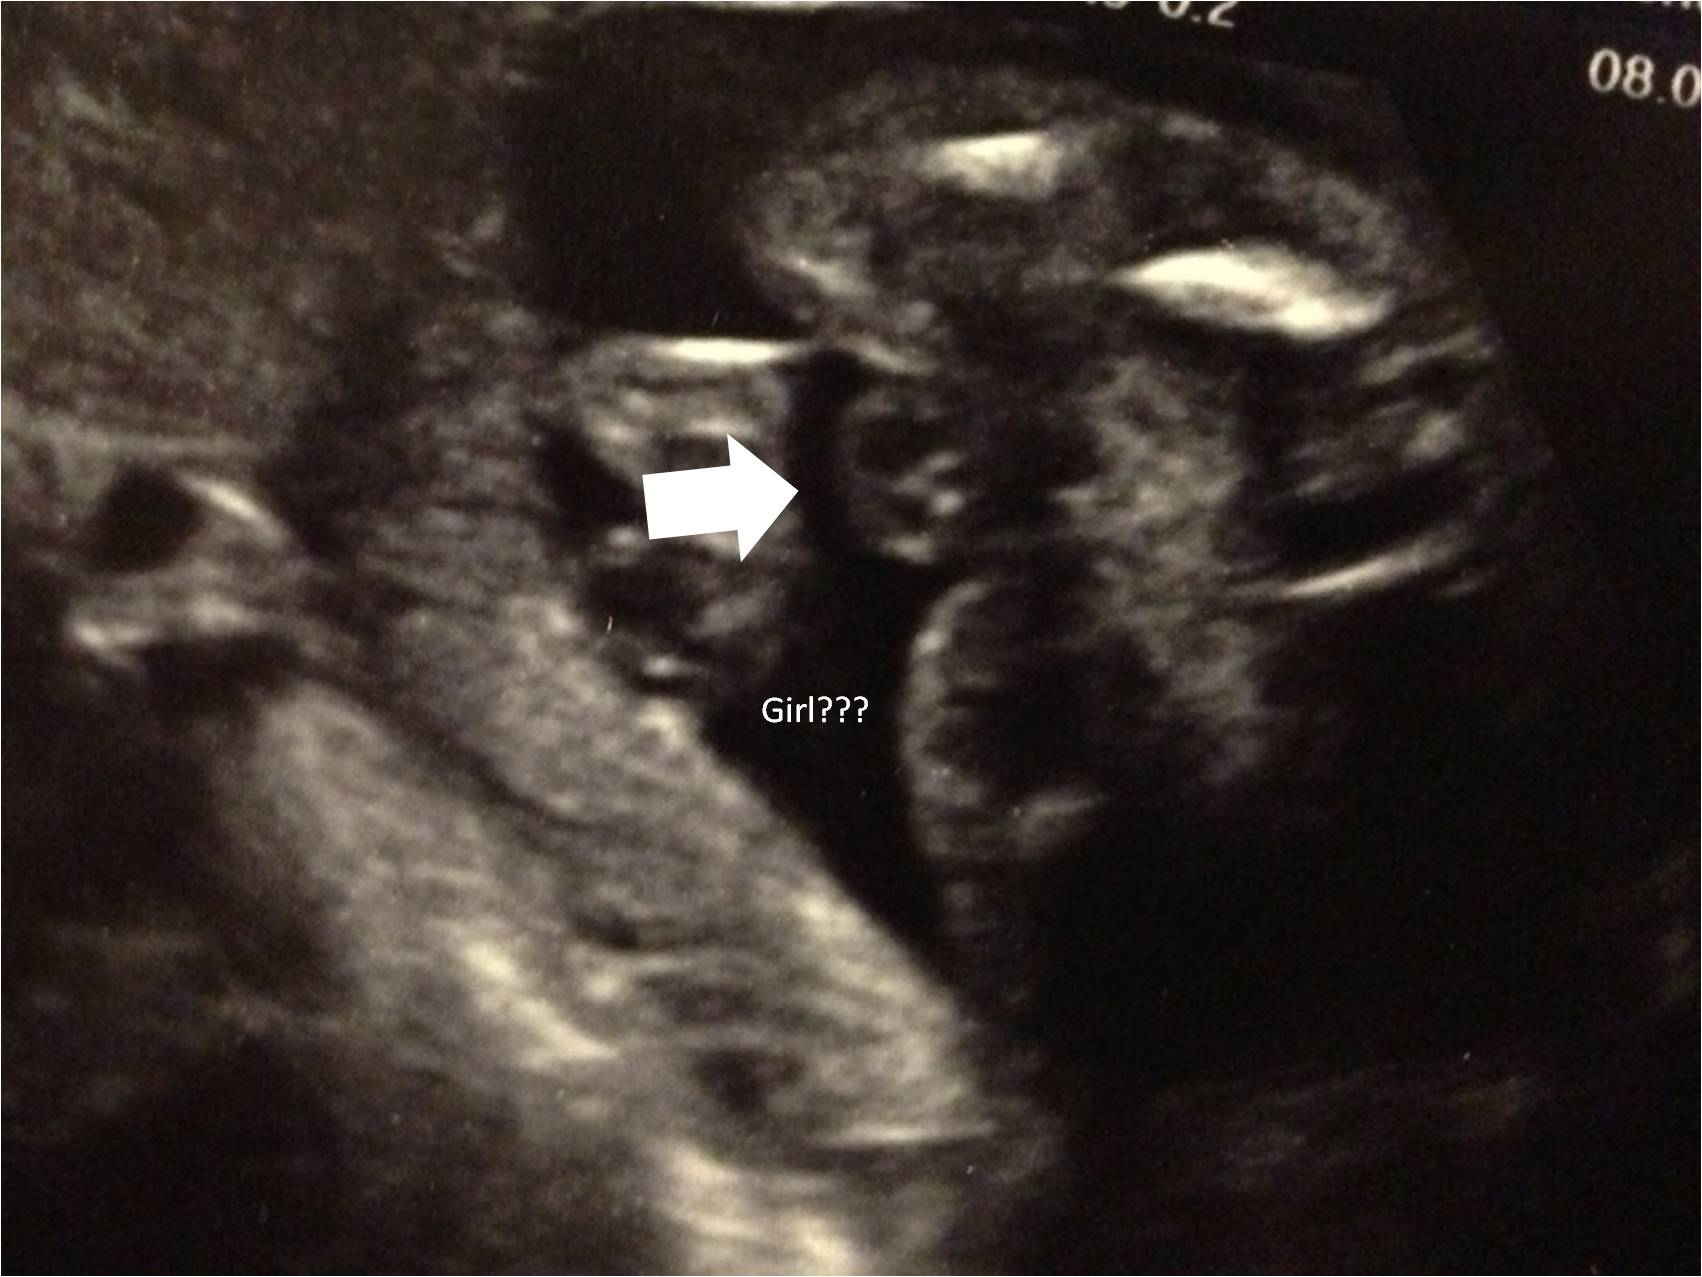

Hello :-) Is that a Boy ore a Girl? Tec said Girl I am confused -> What is the "big thing" that should be the Girl parts ??? (19 Weeks 4 Days pregnant) Thanks :-)))

Congrats that's 100% a girl, what your arrow is pointing at is her labia or lips that's a fantastic "potty shot"